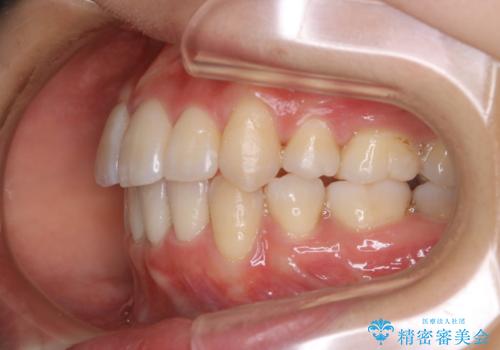

奥歯の上下のズレ等は軽度で、必要なスペースと抜歯により作られるスペースがほぼ等量だったため治療の単純化が計れ、大きな移動・見た目の劇的な変化に対して比較的早期での治療完了となりました。

叢生の度合いが重く、抜歯が必要なケース。八重歯の部分以外には大きな問題は認められなかったため、劇的変化が起こる治療でも比較的短期間で終了することができました。